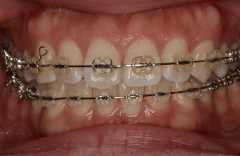

上下奥歯も含めた透明ブラケット矯正による治療例

上下すべての歯に透明なブラケットをつけて全体的な治療を行っています。